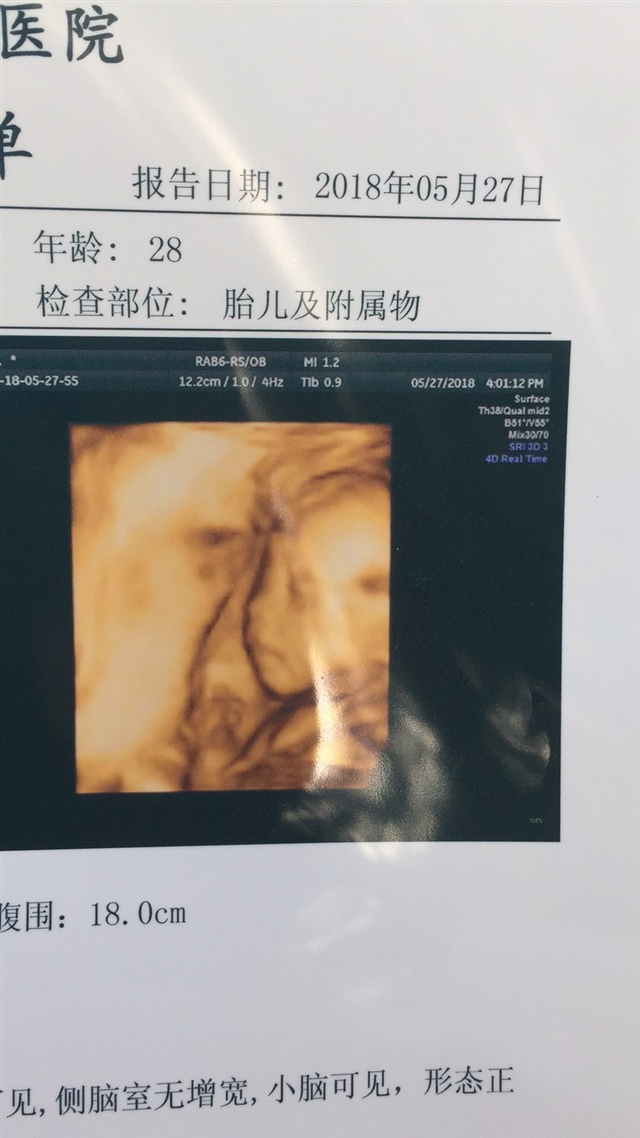

备孕中

宝宝24天

我也是球拍状胎盘,外加脐带绕颈和臀位,不过为了保险医生让提前住院剖腹产了,现在宝宝很健康

じAAご志文超市つ[帖主]:谢谢。不过我这个才五个半月,但是脐带不绕经

我的结果跟你一样!没什么大问题!不用担心!这种情况应该就是生的时候顺产可能会有些麻烦!

じAAご志文超市つ[帖主]:是呢医生说🉐️刨妇产

我也是球拍状胎盘。四维查的。医生也是这么说的。可能生个时候要注意下。没事的。这种情况也有很多的。

じAAご志文超市つ[帖主]:没办法,只能到足月的时候刨